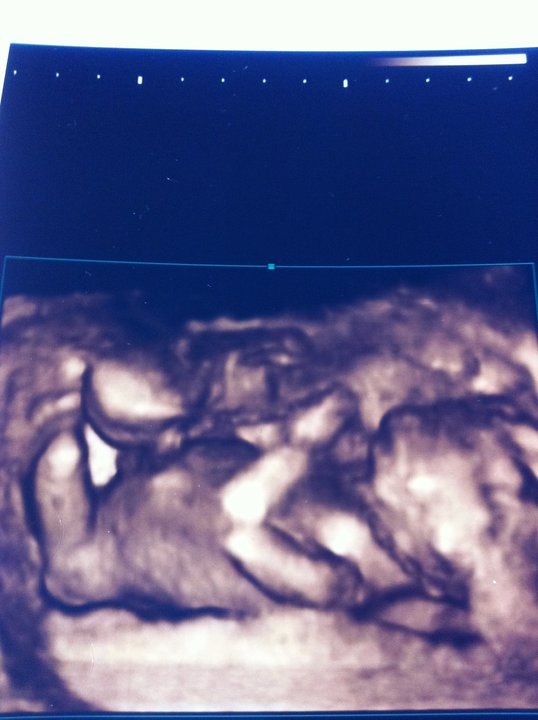

Her er et billede af dagens kønsskanning, synes det er fascinerende at se hendes tæer, værende med på billedet

PIGE!!!!!!!!!!!!!!!!!!!!!!!!!!!!!!!!!!!!!!!

Er det ikke søøødt?! Faren er meget stolt og glad, han har fra start valgt navnet, Nikoline - så det ER en Nikoline Vi får!!

Jeg er selvfølgelig også en meget glad, stolt og lettet moar, for hun var såå livlig, fin, hoppende og dejlig! Det danner en helt ny tilknytning og også personlighed på babyen, at det er en HENDE og ikke en "den" længere